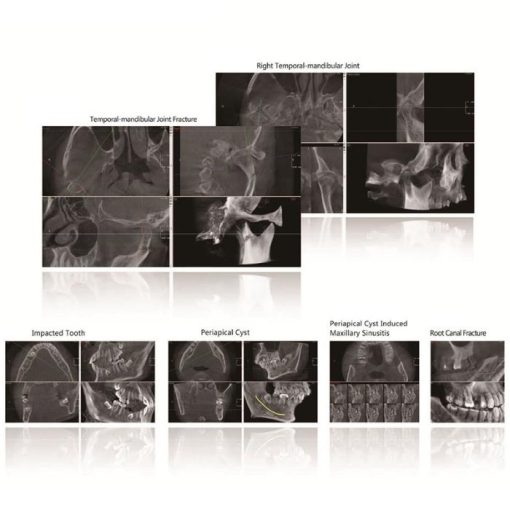

Presently is the most promising and revolutionary device of oral and skull imaging equipment. Its X-ray generator will move around the object for annular DR with low radiation, and after radiograph around the object for times, the jointed data will be reconstructed by the computer to get the 3D image. The application of CBCT has epoch-making meaning to oral health.

High Resolution Digital Image Chain

Digitalization mouth unit adopts unique HRBPR image reconstruction and WE image processing algorithm, and based on the super speed image reconstruction of CUDA technology, the NL-means image smoothing algorithm, and metal artifacts reduction algorithm etc, it provides the users 3D oral images with high resolution and high precision. Meanwhile, the applied pulse source technology can reduce the radiation level for patient and extend the lifetime of X-Ray tube.

Specialized 3D Diagnosis Software

- The processing speed problem is solved by adopting advanced CUDA computing technology and the tomographic images will be generated after 10s.

- After identify the metal area and reconstruct the image for second time, the metal artifacts will be reduced effectively through second reconstruction overlying.

- The similarity of adjacent pixels is considered during image smoothing, which preserves the image details effectively at the same time.